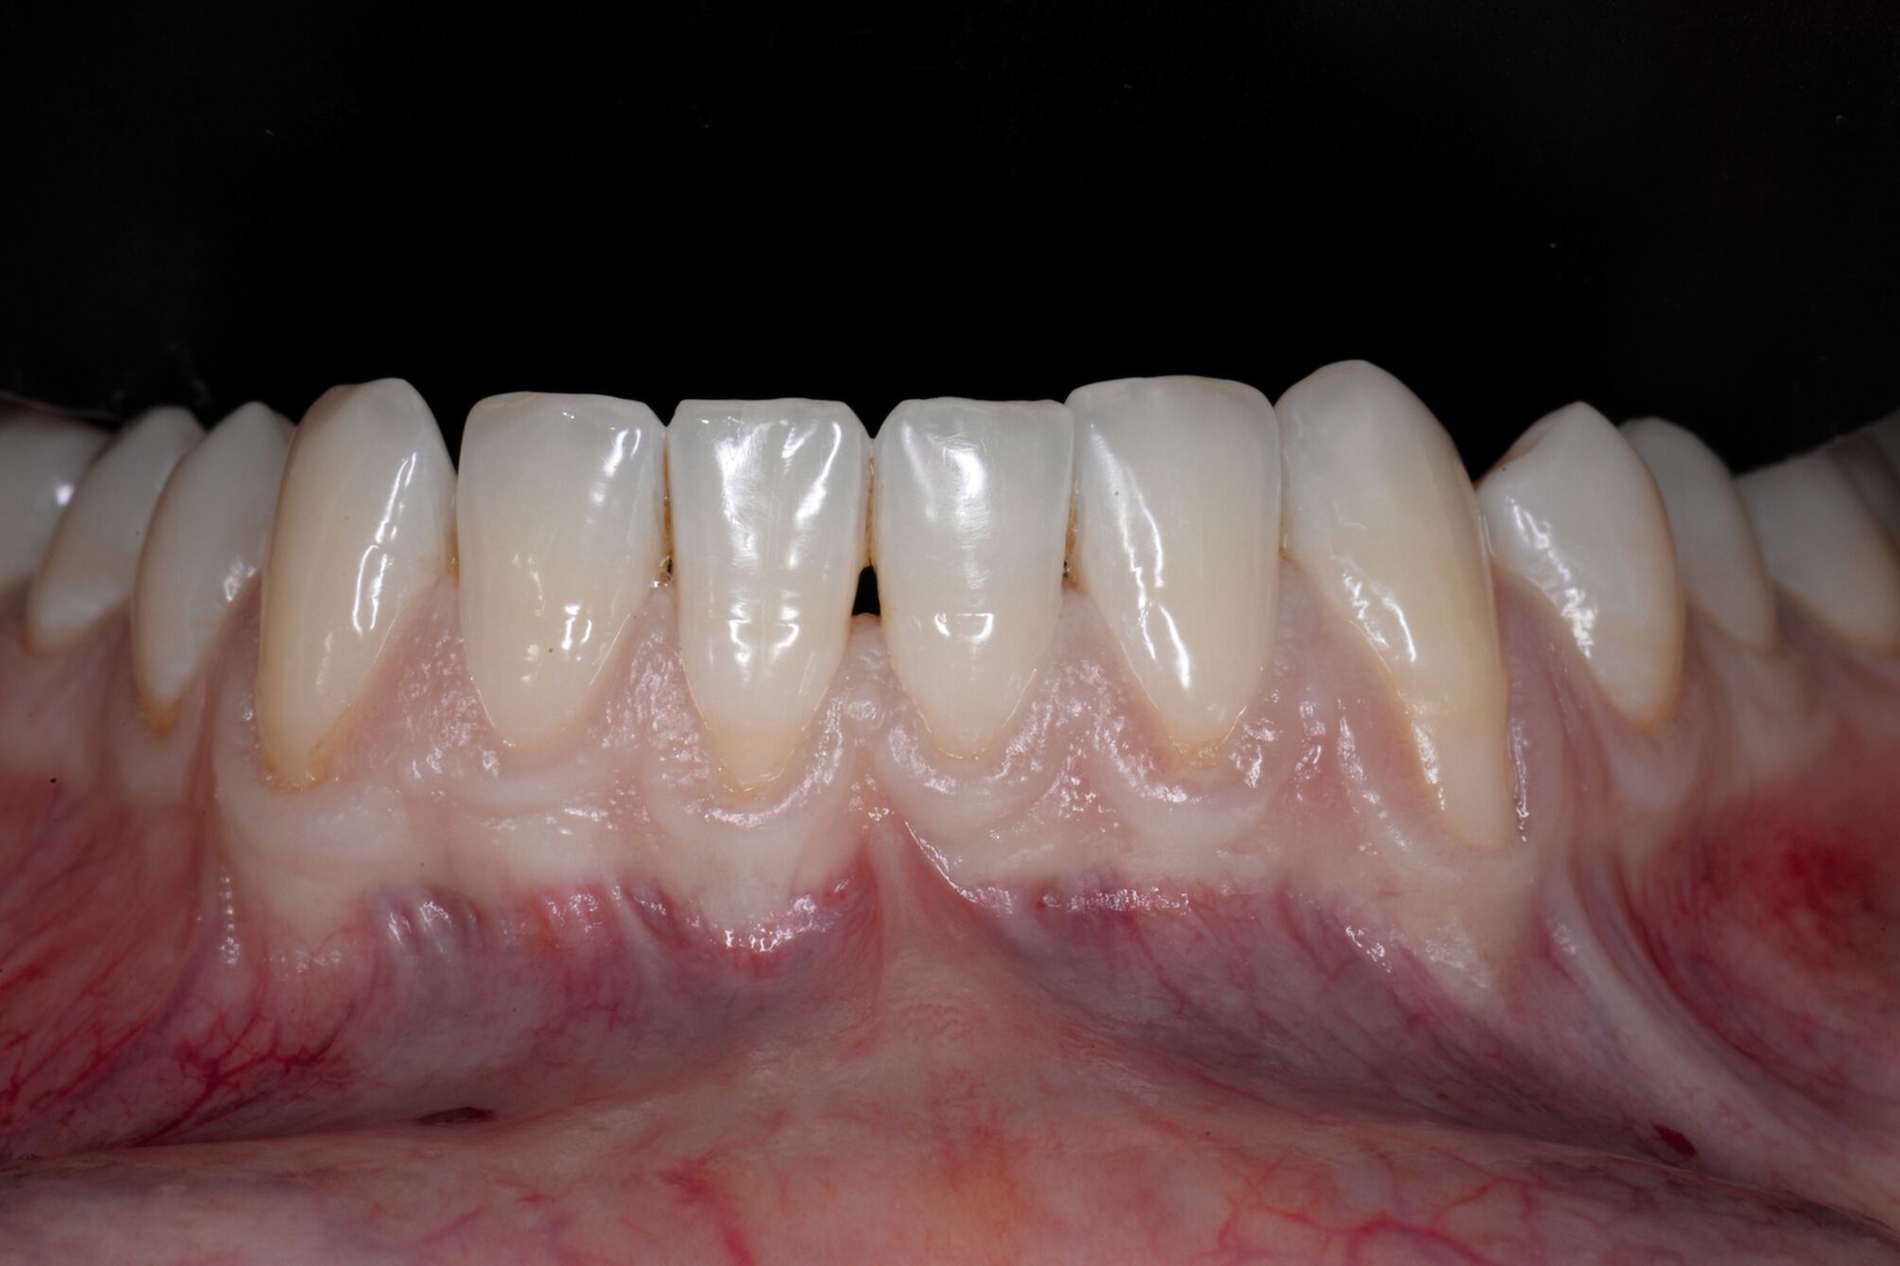

Tunkel et al. versuchten die Vorteile von Zucchellis Koronalem Verschiebelappen und Sculeans Lateral Geschlossenem Tunnel in einer Technik zu vereinen: dem Lateral Geschlossenen Koronalen Verschiebelappen (LCAF) [Tunkel et al., 2024] (Abbildung 3). Bei dieser Methode, mit der vor allem tiefe singuläre parodontale Rezessionen behandelt werden, wird die Koronalverschiebung ohne Entlastungsinzisionen kombiniert mit dem lateralen Verschluss der tiefen parodontalen Rezession.

Das Vorgehen ist hier wie folgt: Zunächst wird im Bereich der tiefen Rezession der Gingivarand geringfügig exzidiert, um ein Zusammenwachsen der geschlossenen Lappenanteile zu ermöglichen. Anschließend wird der Schnitt in horizontaler Richtung durch leicht bogenförmige Schnittführungen auf Höhe der Schmelz-Zement-Grenze erweitert, um mindestens zwei Zähne rechts und links von der Rezession (Abbildung 3b). Im Unterkiefer-Frontzahnbereich, wo die Rezessionen heutzutage am häufigsten vorkommen, sollte der Lappen mindestens von Eckzahn zu Eckzahn gebildet werden, um ein harmonisches Ergebnis nach Abheilung zu erreichen. Auf vertikale Entlastungsinzisionen kann komplett verzichtet werden. Anschließend erfolgt die Lappenpräparation nach dem bereits für koronale Verschiebelappen gängigen Prinzip teilschichtig-vollschichtig-teilschichtig.

Die Papillenbereiche werden mit dem Skalpell scharf vom Periost abgelöst. Dann wird das Periost durchtrennt und bis zur mukogingivalen Grenze ein vollschichtiger Lappen gebildet. Nach Überschreiten dieser wird wieder zweischichtig präpariert. Hierdurch wird eine gute Mobilisation des Lappens erreicht, die eine ausreichende Koronalverschiebung ermöglicht. Entgegen dem in früheren Jahren propagierten komplett teilschichtigen Vorgehen, kann durch dieses Verfahren die Gefahr von Lappenperforationen signifikant gesenkt werden, da diese insbesondere im Bereich der mukogingivalen Grenze auftreten. Nachdem die Lappenareale mesial und distal der Rezession gelöst sind, können diese durch zwei bis drei feine monofile Nähte miteinander verbunden werden (Abbildung 3c). Sobald durch diese Naht ein zusammenhängender koronaler Verschiebelappen entstanden ist, werden die Papillenbereiche koronal des gebildeten Lappens entepithelialisiert. Nach Entnahme eines Bindegewebstransplantats oder entepithelialisierten freien Schleimhauttransplantats wird die Wurzeloberfläche mit EDTA-Gel konditioniert und anschließend werden Schmelz-Matrix-Proteine aufgetragen (Abbildung 3d). Diese bewirken die Bildung eines new attachment und fördern zudem die Wundheilung, was gerade bei den delikaten lateralen Verschiebelappen von Vorteil sein sollte [McGuire und Cochran, 2003; Almqvist et al., 2011; Thoma et al., 2011; McGuire et al., 2016]. Anschließend wird das Transplantat durch Nähte ausgehend vom oralen Papillenbereich fixiert (Abbildung 3e). Zuletzt wird der Lappen mit sogenannten doppelten Umschlingungsnähten im Bereich der Papille durch Zug nach koronal und oral fixiert, was eine perfekte Positionierung ermöglicht [Zuhr et al., 2009] (Abbildung 3f). Hierbei muss darauf geachtet werden, dass der Lappen die Schmelz-Zement-Grenze um mindestens 2 mm überdeckt, um eine hundertprozentige Wurzeldeckung erwartbar zu machen [Pini Prato et al., 2005].

Der Lateral Geschlossene Koronal Verschobene Lappen ermöglicht eine annähernd narbenfreie Deckung singulärer parodontaler Rezessionen durch Verzicht auf vertikale Entlastungsinzisionen (Abbildung 3g). Das Lösen der Papillen im Rahmen der Verschiebung ermöglicht eine deutliche Anhebung des Lappens und somit durch großzügige Überdeckung das Erreichen vollständiger Wurzeldeckungen. Durch den lateralen Verschluss im Rahmen der tiefen, über die mukogingivale Grenze hinausgehenden Rezession kann keratinisierte Gingiva im Bereich dieser hergestellt und eine übermäßige Mobilisation und damit Einschränkung des Vestibulums verhindert werden.